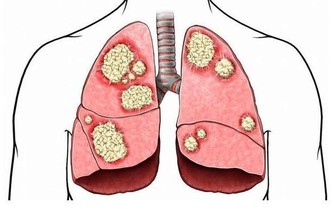

6、排尿疼痛

排尿疼痛專指排尿時出現的劇烈疼痛,尿液有時還帶有鐵鏽色。

可能疾病:

膀胱感染或膀胱癌。疼痛和血尿是膀胱癌的典型症狀,及早發現,治癒的可能性很高。

如何解決:

驗尿能排除細菌感染;如果是膀胱腫瘤,可以通過手術治療,或接受放療和化療。